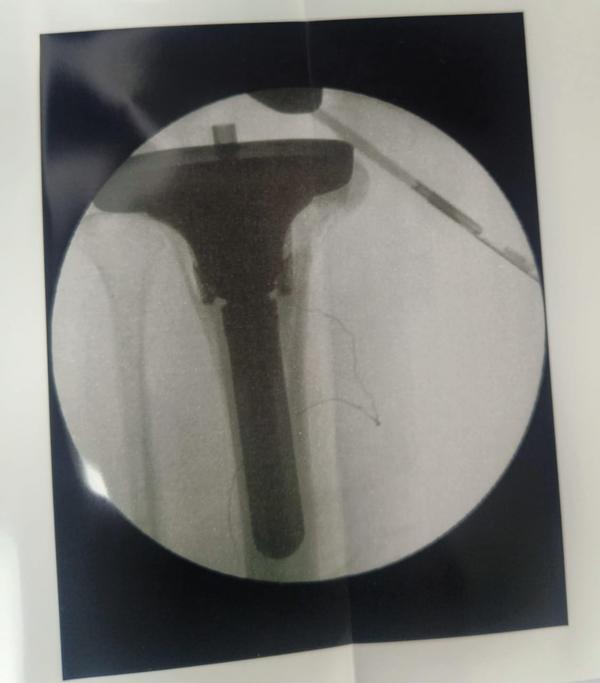

Revision Hip And Knee Replacement

Dr Randive has 25 years experience in Revision Knee and Revison Hip Replacement surgeries. It took him more than 25 years of training hard work and thousands of surgeries to achieve excellence in Revision Knee and Hip Surgeries. He has successfully achieved this milestone through extensive training.